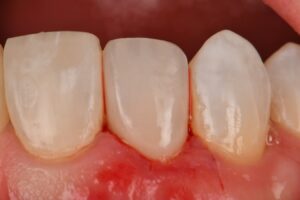

Simple 3 tooth combination direct-indirect restorations on teeth #7, 8 and 9 with pre-prosthetic surgical crown lengthening. The latter two were completed using Voco Amaris.

#IPSemax #VocoAmaris #TSE Ivoclar VOCO VOCO GmbH – The Dentalists Shinichiro Tsuji